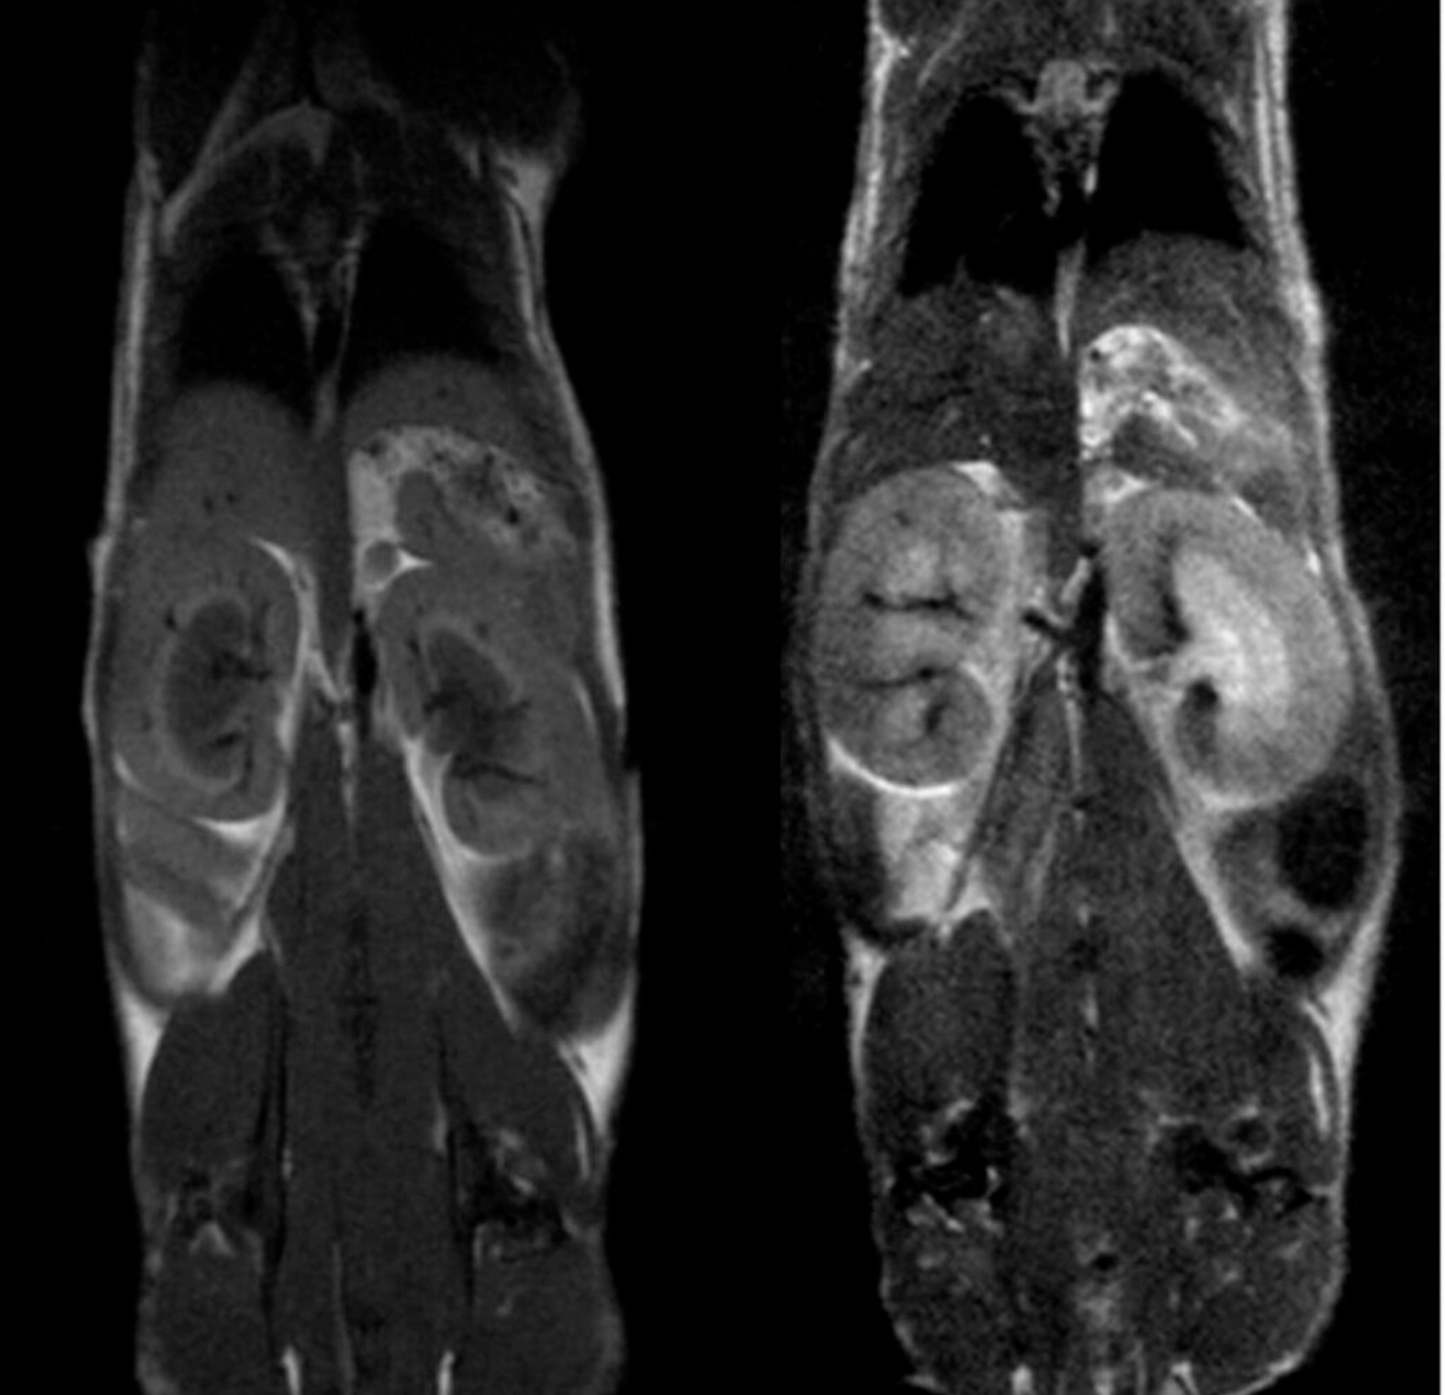

High Performance Preclinical Magnetic Resonance Imaging (MRI) Mice, Rats & Other Small Animals

The M-Series™ systems are cryogen/cooling-free, self-shielded, high-performance MRI systems based on permanent magnet technology. The M-Series systems allow preclinical researchers, with or without in-depth knowledge of MR physics, to utilize the gold standard method in soft tissue imaging without the cost, complexity, and technical burden of superconducting MRI systems. Varying-sized models allow for imaging of mice, rats, similarly sized species/samples, as well as brains of non-human primates. Based on the permanent magnet technology, there are no special infrastructure requirements, operating and maintenance costs are minimal, and they can be easily integrated into existing lab space. These 1 Tesla systems are optimized for anatomical, functional, and molecular imaging applications in cancer, cardiac, neuroscience, and multimodal imaging. The optional SimPET insert can be integrated with the M-Series for simultaneous PET/MRI acquisition.